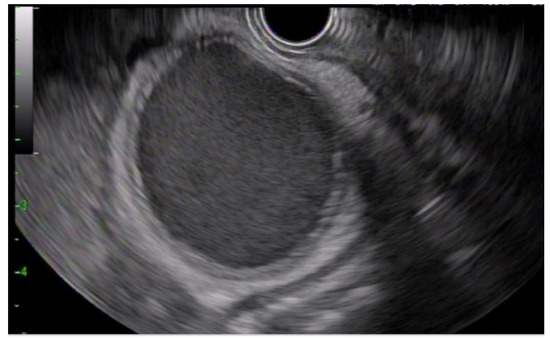

2.4. Procedure Detail